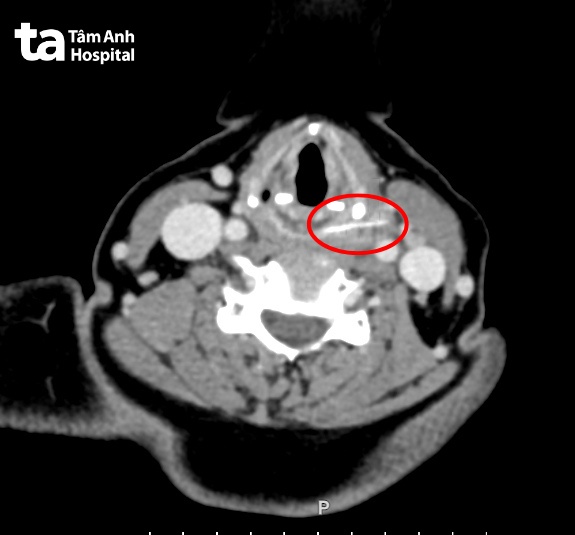

Tại Bệnh viện Tâm Anh TP HCM, chụp X-quang cột sống cổ nghiêng, bác sĩ nghi ngờ có dị vật vùng mặt sau sụn nhẫn (bộ phận của thanh quản). Sau đó bác sĩ chỉ định chụp CT vùng cổ cho thấy một vật hình que dài khoảng 3 cm, đâm xuyên thành sau hạ họng vào lớp cơ cổ bên. Quanh dị vật có dấu hiệu viêm, tụ dịch, vùng cổ trái đã áp xe.

ThS.BS.CKII Trần Thị Thúy Hằng, Trưởng khoa Tai Mũi Họng, Trung tâm Tai Mũi Họng, cho biết vị trí hóc xương cá ở sâu (ngang miệng thực quản đi xuống), lại nằm ngay phía sau sụn nhẫn nên khó phát hiện. Hình dạng xương cá dài nhưng mỏng, chụp CT cắt lớp dày có thể bỏ sót dị vật.